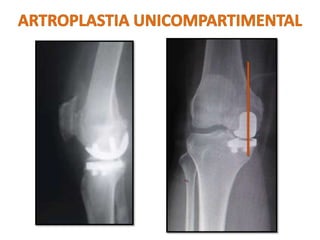

Osteoartrose

unicompartimental

– 80% resultados

satisfatórios – 5anos

– Fundamentação

biomecânica

Comprometimento medial

ou lateral

Idade > 55 anos

Baixa demanda

Peso < 82 KG

Mínima dor ao repouso

ADM > 90 °

Flexo < 5 °

Valgo < 15 ° corrigível para

neutro

Artrite Inflamatório

Alta demanda

Dor em repouso

Comprometimento

patelofemoral – sintomático

LCA deficiente – Lateral

Osteonecrose secundária

INDICAÇÕES CONTRA-INDICAÇÕES